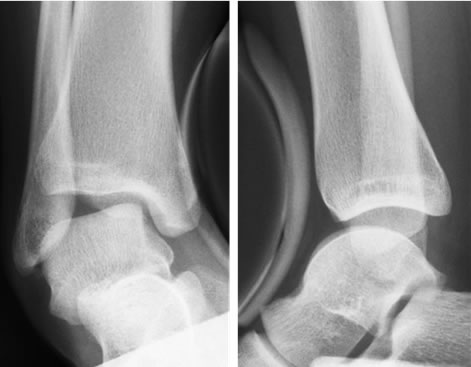

変形性足関節症

変形性足関節症の初期症状は、長時間歩行後の腫れや痛みや歩き始めの動かしづらさが主です。関節変形の進行とともに、凸凹面を歩く際の不安定感や早歩きや階段・坂の歩きにくさなどが出現し、痛みや腫れも起こりやすくなって立っているだけの時や安静時の痛みが起こることもあります。